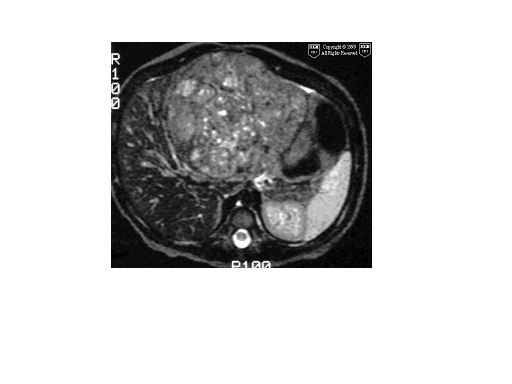

肝母细胞瘤(hb)好发年龄在3岁以下,以1岁以下为多见,与乙型病毒性肝硬化无关,90%以上甲胎蛋白阳性明显升高,钙化占肿瘤38%~50%,由于肝母细胞瘤生长迅速,在肿瘤区域可出现不同程度坏死、出血或纤维瘢痕。

肝细胞癌 发病年龄高峰为4岁及12~15岁,男女之比约为1.3,与hbv感染、肝硬化有关。组织形态上,分化好的肝细胞癌可见到一些肝细胞的特征。

下面上传经病理证实的hb